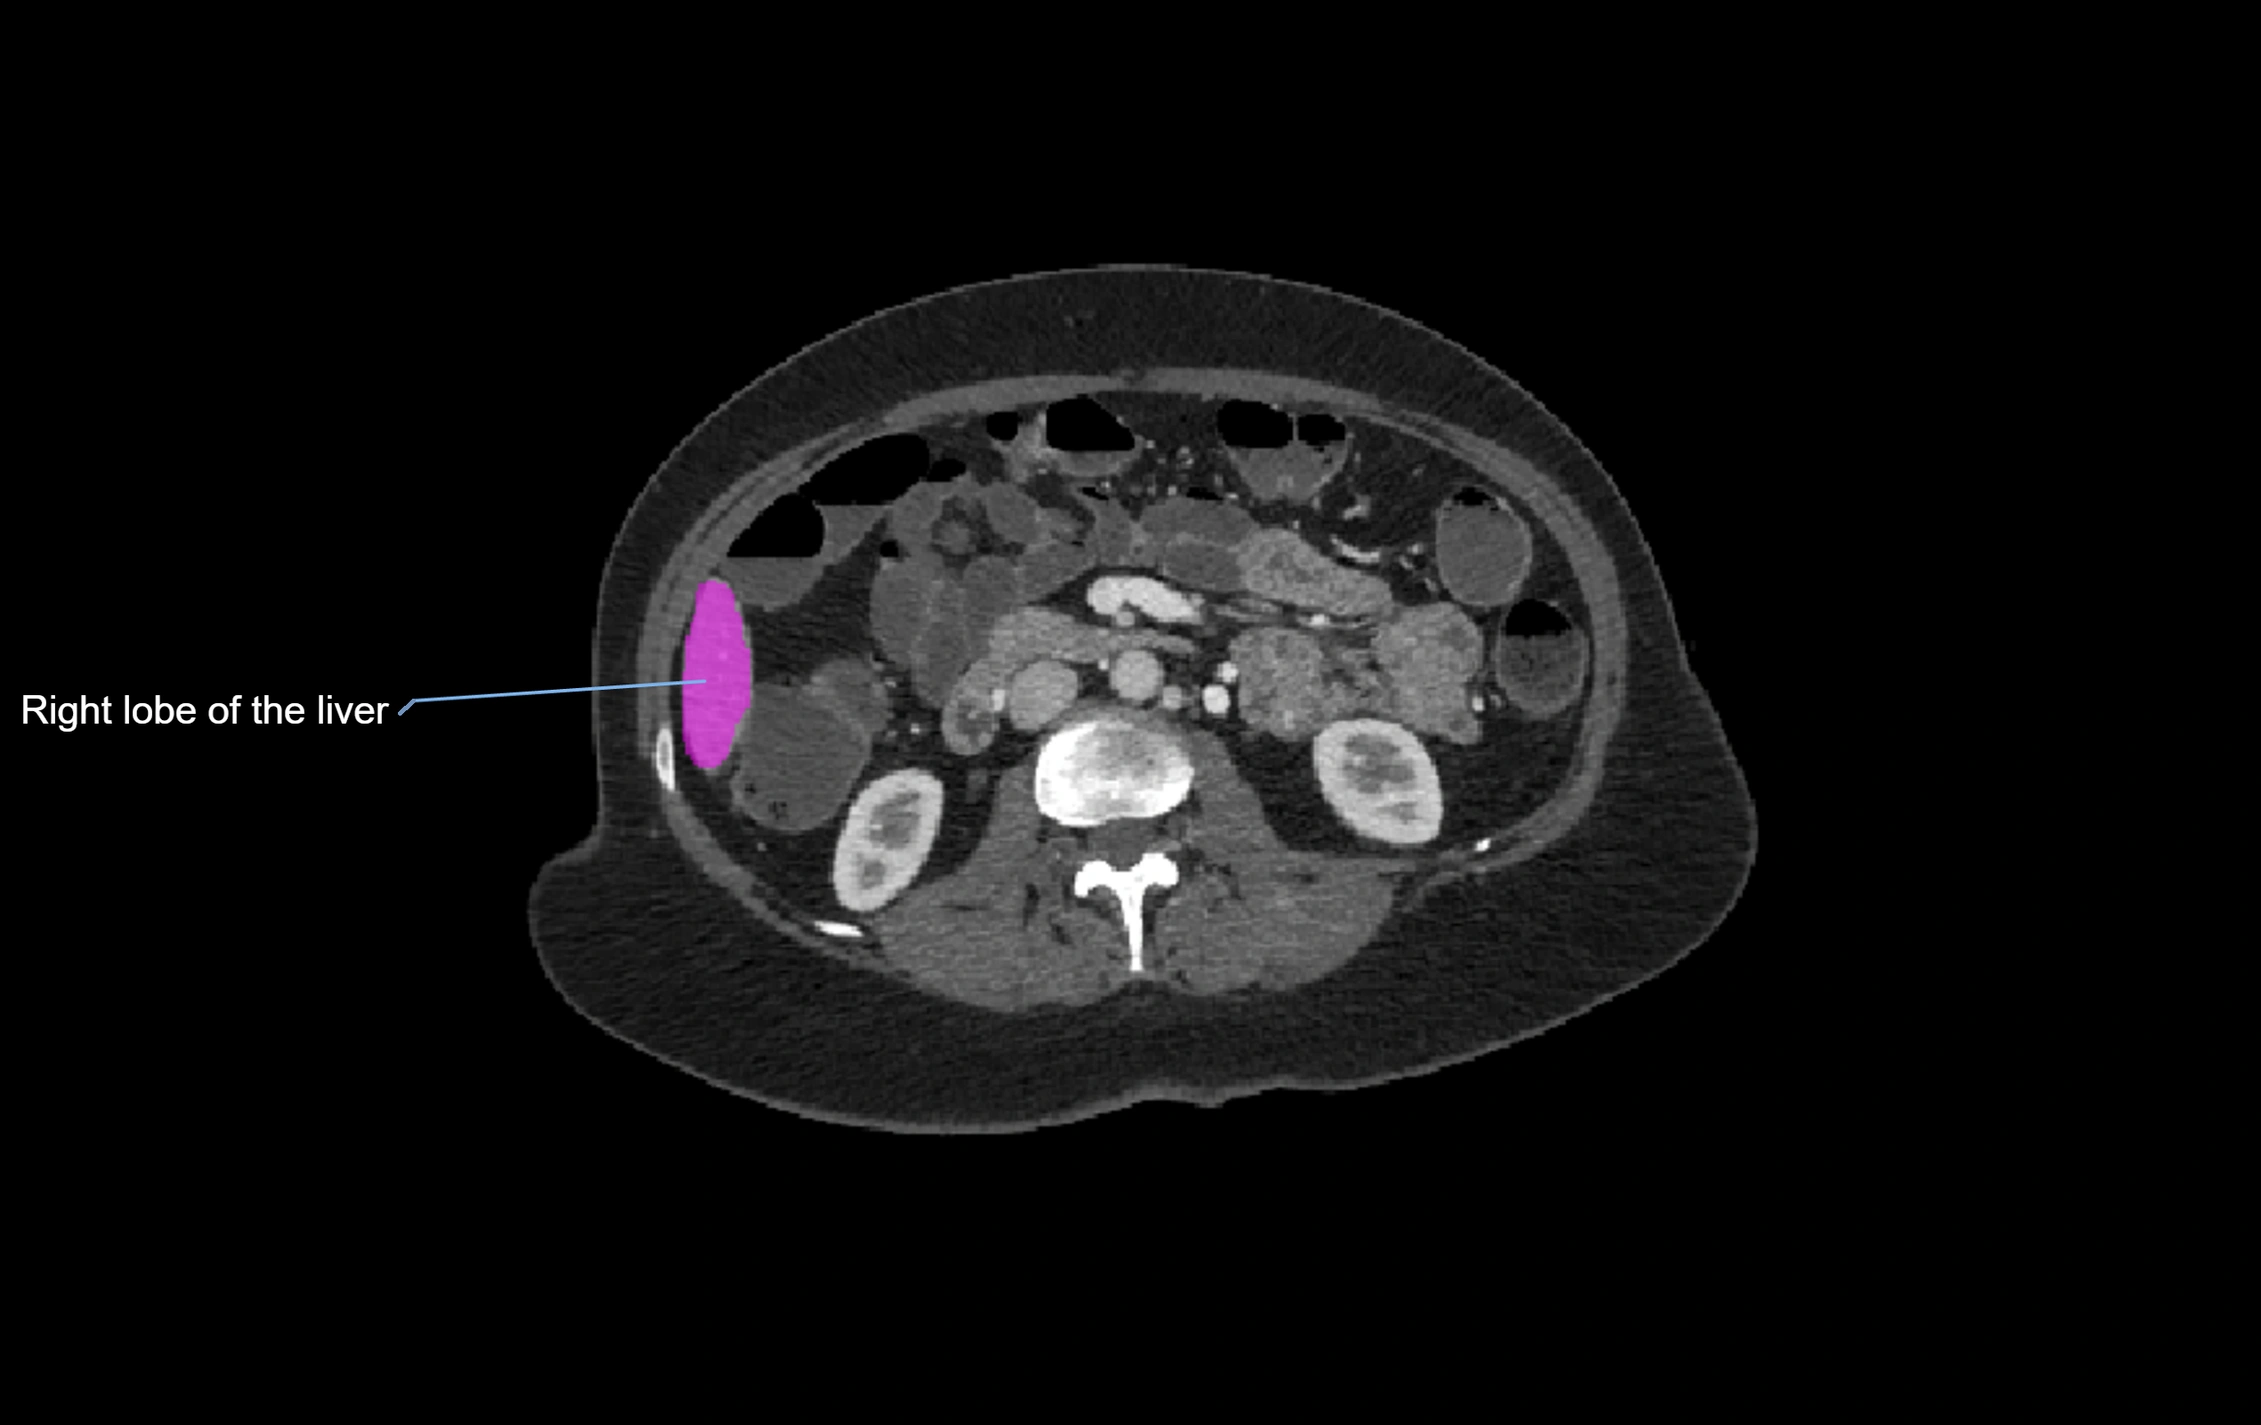

CT Image

image